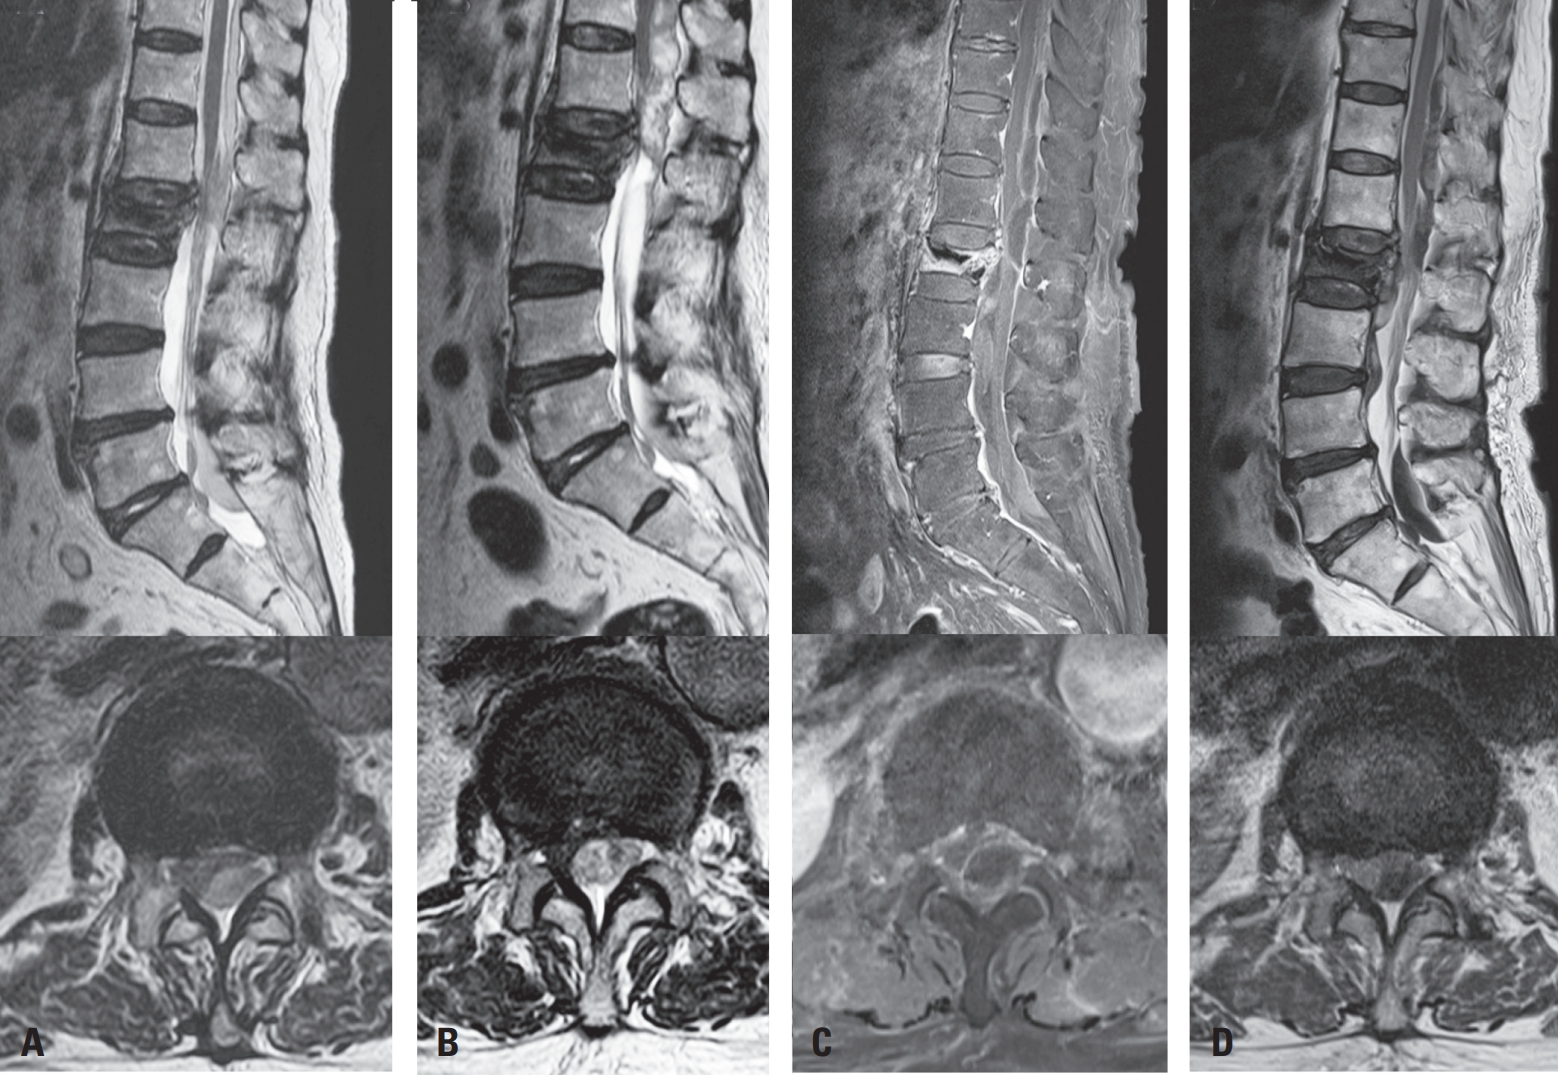

In our case, review of intraoperative fluoroscopic imaging revealed that during the left-sided needle insertion, the needle did not fully traverse the vertebral body in the lateral view, suggesting possible medial wall violation (Fig. 3A, B). Postoperative X-ray also demonstrated a very mild posterior cement leakage, which was initially overlooked due to its subtle appearance. On postoperative day 1 MRI, medial pedicle violation was suspected (Fig. 3C), and subsequent computed tomography performed after transfer to our institution demonstrated cement leakage into the spinal canal (Fig. 3D). These findings indicate that medial deviation of the needle, in combination with anticoagulation therapy (warfarin and enoxaparin), likely contributed to the development of the subdural hematoma.6,15)

Fig. 3.

Imaging suggesting medial pedicle breach and cement leakage. (A, B) Intraoperative fluoroscopic images (AP and lateral views); the needle does not fully traverse the vertebral body in the lateral view (white arrow), suggesting possible medial wall violation. (C) Postoperative day 1 MRI showing suspected medial pedicle breach (white arrow). (D) Post-transfer CT confirming cement leakage into the spinal canal (white arrow).

Fig. 3. Imaging suggesting medial pedicle breach and cement leakage. (A, B) Intraoperative fluoroscopic images (AP and lateral views); the needle does not fully traverse the vertebral body in the lateral view (white arrow), suggesting possible medial wall violation. (C) Postoperative day 1 MRI showing suspected medial pedicle breach (white arrow). (D) Post-transfer CT confirming cement leakage into the spinal canal (white arrow).